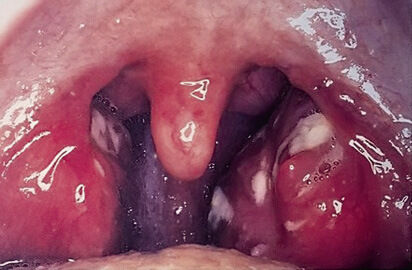

¿Qué complicaciones pueden presentarse en IVAS mal tratadas? Otitis media, sinusitis bacteriana, abscesos periamigdalinos, fiebre reumática (en faringitis estreptocócica), glomerulonefritis postinfecciosa.

¿Qué hallazgos sugieren neumonía en la exploración física? Estertores crepitantes, matidez a la percusión, aumento del frémito vocal, egofonía, disminución del murmullo vesicular.